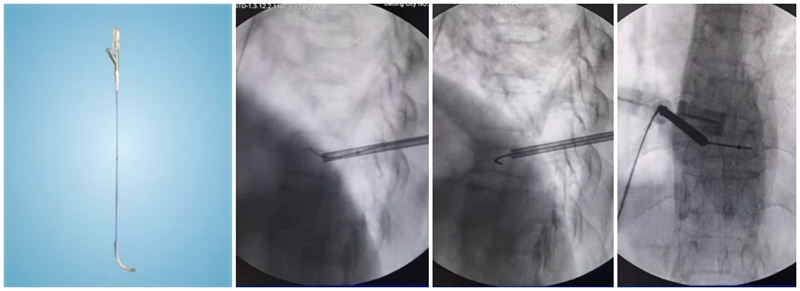

(3)弯角骨钻扩张:C形臂X线机正位透视下,弯角骨钻开腔器械螺旋手柄顺时针扭转,让弯角骨钻沿导丝前进开路,将椎体内部钻出弧形通道。操作中注意骨钻沿导丝旋进旋出要完全,旋进不够,后期球囊无法到达对侧,旋出不完全,骨钻会卡在工作套筒上无法拔出。

(4)置入球囊:插入带导丝弯角球囊时注意透视球囊方向,反复调整务必与终板平行。如需要拔出球囊调整方向,务必先拔导丝再拔球囊,透视球囊标记点必须完全从工作套管内出来,否则易造成弯角球囊与工作套管边缘卡磨破裂。

(5)扩张球囊:注入造影剂扩张球囊过程中,注意观察术中正侧位透视图像,控制压力值,不必苛求球囊顶到上下终板,以免发生医源性终板破裂,造成椎间隙骨水泥渗漏可能。注意弯角球囊扩张完毕后拔除顺序:先拔导丝再拔球囊。